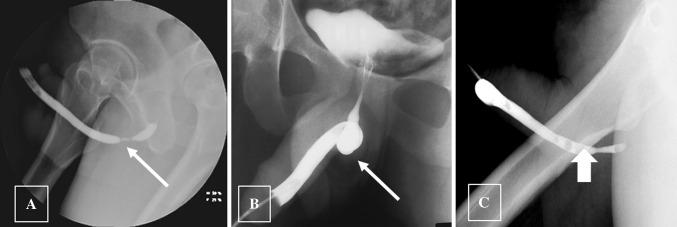

To discuss the imaging appearances of various pathologies affecting adult male urethra and to review the role of imaging in the assessment of artificial urinary sphincters and penile prostheses. Diagnosis of common male urethral diseases heavily depends on two conventional fluoroscopic techniques namely retrograde urethrography and voiding cystourethrography. These are useful in evaluating common urethral diseases like traumatic injury, infections, and strictures. Cross-sectional imaging can be useful in evaluating periurethral pathologies. Artificial urinary sphincters, slings, and periurethral bulking agents are used in the management of urinary incontinence and imaging can be utilized to detect complications in these devices. Cross-sectional imaging especially MRI plays a significant role in evaluating the different types of penile prostheses and their malfunctioning.

讨论影响成人男性尿道的各种病变的影像学表现,并回顾影像学在评估人工尿道括约肌和阴茎假体中的作用。常见男性尿道疾病的诊断主要依赖于两种常规的荧光透视技术,即逆行尿道造影和排尿性膀胱尿道造影。这些技术在评估外伤性损伤、感染和狭窄等常见尿道疾病方面非常有用。横断面成像可用于评估尿道周围病变。人工尿道括约肌、吊带和尿道周围填充剂用于治疗尿失禁,影像学可用于检测这些装置的并发症。横断面成像,特别是 MRI,在评估不同类型的阴茎假体及其故障方面发挥着重要作用。